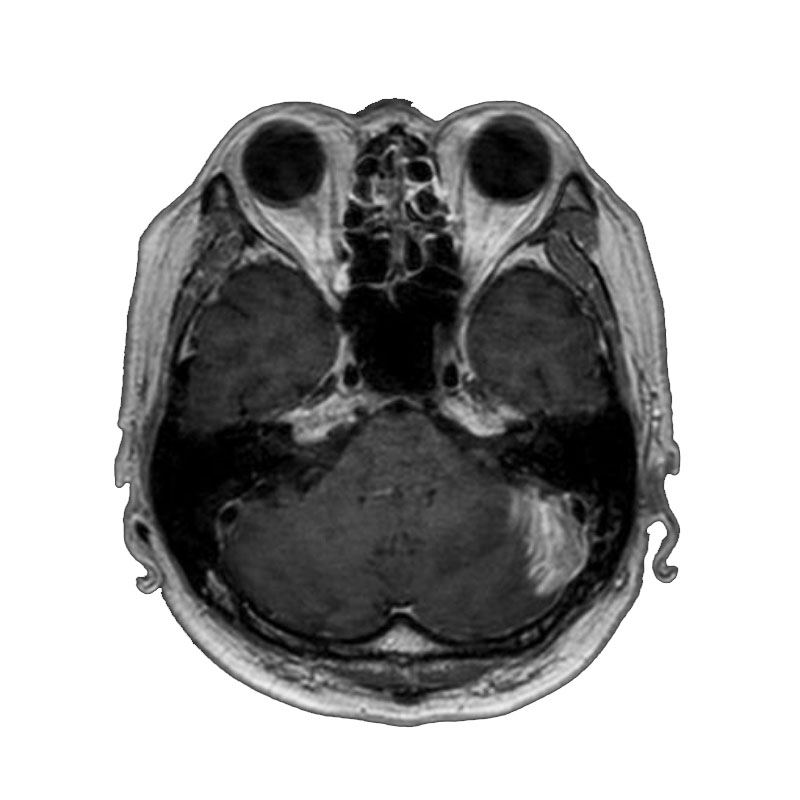

画像